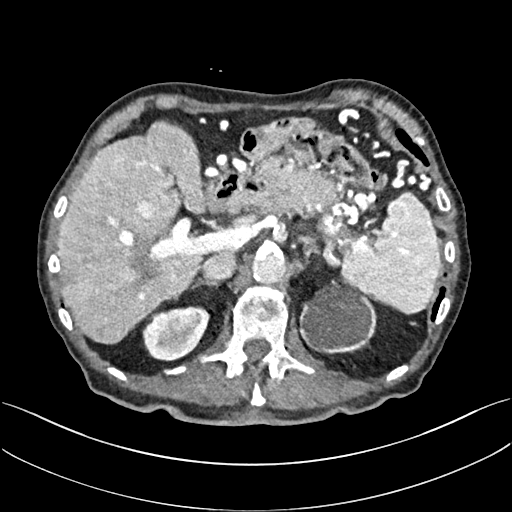

To demonstrate the effectiveness of the proposed network, we perform the qualitative comparisons over three representative abdominal images presented in Figs. 3, 5 and 7. For better evaluations of the image quality with different denoising models, zoomed regions-of-interest (ROIs) are marked by red rectangles and shown in Figs. 4, 6 and 8 respectively. Note that all results from different denoising models focus on two aspects: content restoration and noise-reduction. All CT images in axial view are displayed in the angiography window [-160, 240]HU.

The real NDCT images and corresponding LDCT images are presented in Figs. 3a and 3b. As observed, there are distinctions between ground truth (NDCT) images and LDCT images. Figs. 3a and 7a show the lesions/metastasis. Fig. 5a presents focal fatty sparing/focal fat. In Figs. 4a, 6a and 8a, these lesions can be clearly observed in NDCT images; in contrast, from Figs. 4b, 6b, and 8b, it can be seen that the original LDCT image is noisy, and lacks structural features for task-based clinical diagnosis. All adopted denoising models suppress noise to some extent.

Mean-based methods can effectively reduce noise, but the side effect is impaired image contents. In Fig. 3c, -net greatly suppresses the noise, but blurs some crucial structural information in the porta hepatis region. Meanwhile, some waxy artifacts can still be observed in Fig. 6c. -net does not produce good visual quality because it assumes that the noise is independent of local characteristics of the images. Even though it retains high SNR, its results are not clinically preferable. Compared with -net, in Figs. 3d and 5d, it can been seen that -net encourages less blurring and preserves more structural information. However, as observed in Fig. 4d, it still over-smooths some anatomical details. Meanwhile, in Fig. 6d, there are some blocky effects marked by the blue arrow. The results obtained by RED-CNN [35] deliver high SNR but blur the vessel details as shown in Figs. 4i and 6i.

For SL-based methods, as observed in Figs. 3e and 5e, SL-net generates images with higher contrast resolution and preserves texture of real NDCT images better than -net and -net. However, Figs. 4e and 6e show that SL-net does not preserve the structural features well, and there still remain small streak artifacts. Subsequently, in Figs. 4e and 4f, SL-net and MSL-net have low frequency image intensity variance because SSIM/MS-SSIM is insensitive to uniform biases [49, 51]. On the other hand, -net preserves the overall image intensity, but it does not preserve high contrast resolution well as SL-net and MSL-net do.

From Figs. 7 and 8, we can see mean-based and SL-based methods work well with effective noise suppression and artifact removal. However, the illustrations in Fig. 8 show that these methods blur the local strutural features. Our proposed SMGAN-based methods present a better edge preservation than the competing methods.